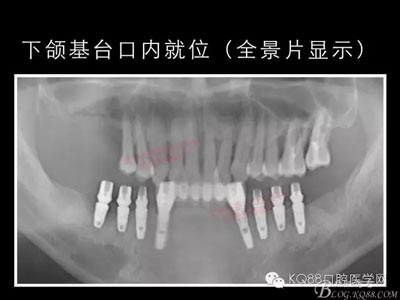

下面的種植病例是為患者提供全口牙齒治療修復(fù)完整過(guò)程的下頜部分,我們門(mén)診和患者共同配合下目前取得了較好的修復(fù)效果,即將開(kāi)始的上頜牙齒治療修復(fù)過(guò)程仍然艱辛。